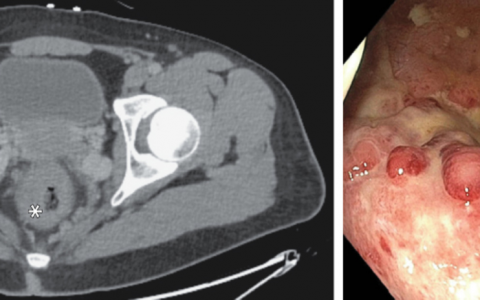

梅毒螺旋体血凝试验呈阳性,快速血浆反应素(RPR)滴度为1:128。右腹股沟皱襞的皮肤活检样本的免疫组织化学染色对梅毒螺旋体呈阳性。诊断为伴有间擦疹的二期梅毒。在免疫抑制的患者中,二期梅毒的皮疹可能非常多变且不典型。